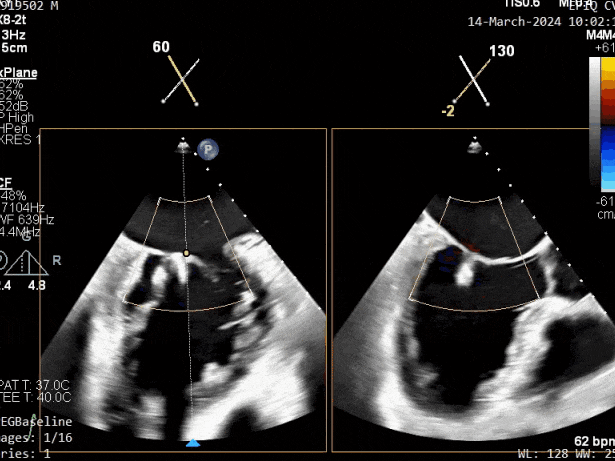

瓣膜夹释放前评估,二尖瓣反流减轻

瓣膜夹释放前评估,二尖瓣平均跨瓣压差及瓣口面积

释放瓣膜夹后评估,二尖瓣呈双孔,外侧仍有残余反流